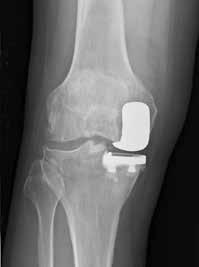

(Top, from left) X-ray images show a normal knee; unicompartment OA with some wearing on inner side of knee; and post-partial knee replacement.

(Bottom, from left)

Tricompartment OA with severe damage to both knees; and post-total knee replacement.

Partial knee replacement

In PKR, or unicompartmental knee arthroplasty, only the damaged portion of the knee joint is replaced with a prosthetic implant made of metal and plastic to restore the natural knee anatomy.

This procedure is typically recommended for younger patients and those with isolated unicompartmental knee osteoarthritis, where only one part of the knee is affected, usually the medial, or inner, compartment. “PKR can provide excellent pain relief and functional improvement for suitable candidates. Success rates are generally high, but long-term outcomes may be influenced by factors such as patient selection and implant longevity,” said Dr Liu.

As with TKR implants, PKR implants can last years — about 10 years for 80 per cent of patients. Longevity, though, may be influenced by factors such as the patient’s age and activity level, and the design of the implant.

With smaller incisions, PKR patients recover faster than TKR patients, and are able to return to normal activities about a month after surgery. They have improved joint function and a lower risk of infection, but have a greater risk of fracture during surgery. Should they need a TKR at a later time, conversion surgery is slightly more difficult than TKR on a native joint.

About 200 PKR procedures are performed yearly at SGH, far fewer than TKR surgeries.